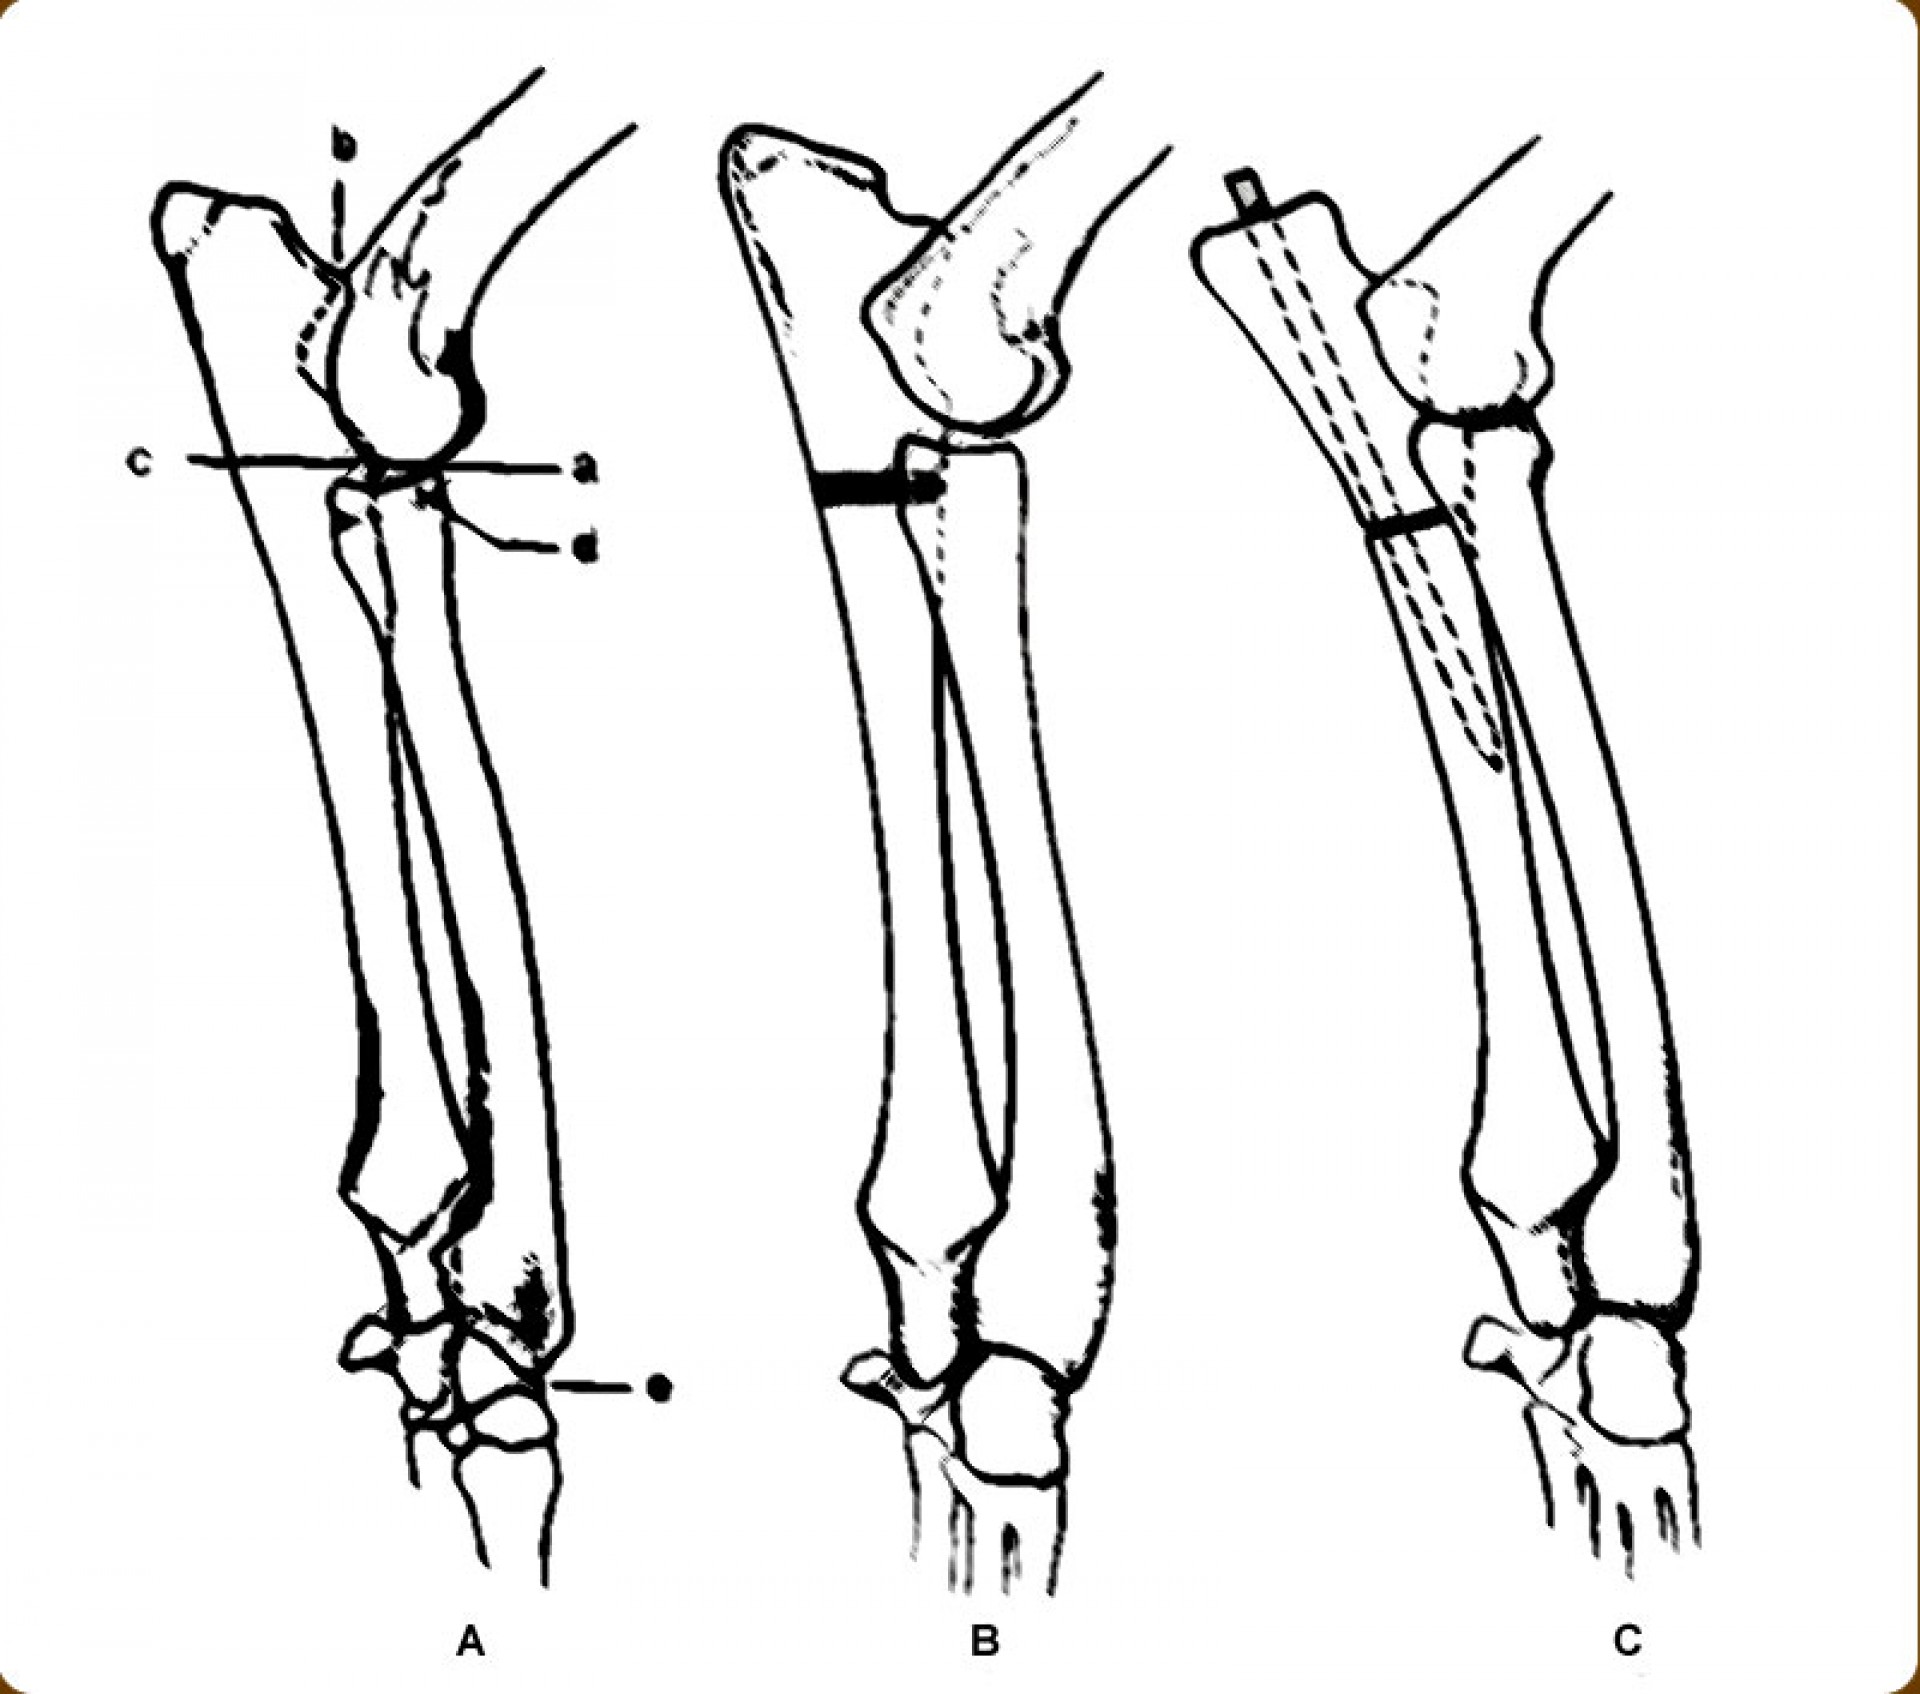

A könyökcsont alsó epiphysisének lezáródása (short ulna) az alkar kifelé történő görbülését eredményezi (valgus állás). A klinikai tünetek (végtagdeformitás) mindig fokozatosan, lassan alakulnak ki, sok esetben a növekedési zóna lezáródásához vezető trauma nem igazolható. Az állat a lábát az elülső lábtőízület alatti területen kifelé fordítva tartja.A fizikális vizsgálat során fájdalom nem tapasztalható és az altatásban történő vizsgálat során a végtag deformitása nem szüntethető meg. A kiegészítő RTG vizsgálattal a könyökcsont alsó növekedési zónájának záródása egyértelműen igazolható. Ezek alapján a betegség az elülső lábtőízület lazaságától (carpal laxity) egyértelműen elkülöníthető. Mivel a végtagállási hiba már kölyök korban megjelenik fontos annak elkülönítése is, hogy örökletes úton (X-láb) vagy a növekedési zóna lezáródása következtében alakult ki a valgus állás.

Amennyiben a növekedési zóna lezáródása a végtag deformitásának oka és idejében felismertük a betegséget, a fékként szolgáló könyökcsont egy darabját eltávolítva (ulna osteotomia) az alkarcsont növekedése normalizálódhat. A lassú gyógyulás elengedhetetlen feltétele, hogy az állat még növendék korban legyen, így az alkarcsontnak is legyen lehetősége a növekedésre.Amennyiben a végtag növekedésére már nincs esélyünk, ill. a valgus állás genetikai vagy egyéb traumás eredetű, a műtéti korrekció során a görbült alkarcsontból egy ék kivágásával és az elvágott területek megfelelő irányba helyezését követően osteosynthesis-sel a végtag kiegyenesíthető.

Az alkarcsont növekedési zónájának záródása általában a könyökízületben un.: inkongruenciát okoz. A könyökízület működéséhez az azt alkotó 3 csont (karcsont, könyökcsont, alkarcsont) tökéletes illeszkedése elengedhetetlen. Azokban az esetekben amikor bármely 2, a könyökízület alkotásában résztvevő csont ízületi felszíne nem illeszkedik tökéletesen,rendellenes ízületi alakulásról, inkongruenciáról beszélünk. Ezekben az esetekben az ízületi felszínek nem megfelelő terhelődése azok kopásához, idült ízületgyulladáshoz, következményesen fájdalomhoz vezet.

Az alkarcsont alsó vagy felső növekedési zónájának lezáródása esetén a könyökízületben kialakuló inkongruencia az ízület mozgásának fájdalmasságához, a mozgáspálya beszűküléséhez vezet. Paradox módon az ilyen elváltozás esetén is (mivel az alkarcsont a teherviselő csont) a könyökcsont osteotomiájával, annak növekedésének korlátozásával gyógyítjuk a beteget.

Az idejében észrevett elváltozás esetén, - amennyiben a csövescsontok növekedése még nem állt le -, az ízület normalizálódik, az eredeti funkció visszaáll.Súlyos fokú inkongruencia kialakulása esetén az ízületi funkció már nem állítható vissza. Azokban az esetekben, amikor a súlyos ízületi elváltozás fájdalommal jár az ízület bemerevítésével (arthrodesis) a fájdalom megszüntethető.